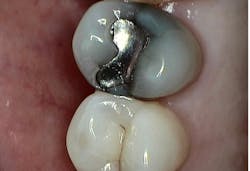

For indirect restorations and restorative foundation codes, a preoperative radiograph is generally required. Notice that the requirement is a radiographic image, not an intraoral photographic image. Some carriers require this preoperative radiograph to be a periapical and some require a periapical x-ray capturing the entire apex to facilitate complete radiographic evaluation of the tooth’s apex and surrounding tissues.

The clinical claim reviewer is looking to confirm that the apical region is free of pathology and being treated appropriately, which can be documented with a final endodontic radiograph for greatest success, or, at minimum, in the narrative. Since capturing the apex does not give us a complete snapshot of the health of the tooth, the clinical crown needs to be evaluated, and this is done either by capturing the coronal structure in the same PA or by providing additional radiographs, more PAs, or, more commonly, a bitewing.

Sometimes, offices provide intraoperative photos and/or radiographs, but these do not meet preoperative radiograph requirements. A common scenario for confusion, resulting in a request for more information, an adverse determination such as a denial, or an appeal, is a case involving a dislodged crown. The PA acquired prior to registering a new impression or scan is preoperative and should be communicated in a narrative. During my peer-to-peer calls, offices would tell me, “The claim form says the prior date for treatment was xx/xxxx,” but without the indication that the crown was lost and the radiograph enclosed is preoperative, a consultant will assume a crown was in place and removed before acquiring the x-ray, which would make the x-ray intraoperative. It’s best to communicate the tooth’s story in your narrative.

If you chose to submit a truly intraoperative photo and/or radiograph, consider what you are trying to demonstrate, remembering that the insurance carrier is not looking to confirm treatment was done but to establish medical necessity for the tooth at the time of treatment. On these peer-to-peer calls, patients would tell me the photos demonstrate the little remaining tooth structure after the filling was removed, but many clinical claim reviewers will say this may be due to an overzealous preparation design. My perspective is that it may be better to capture images of the decay under the filling that was removed, rather than the state of the final preparation.